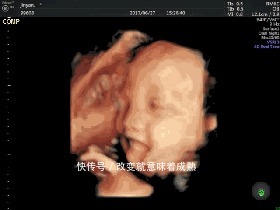

这3种反应要恭喜,胎儿智商高1)小动作不断在孕22-28周时,孕妈需要做一项叫“四维彩超”的检查,来全方面的排查畸形。

四维彩超和前面的B超很不一样,它能清晰的看见宝宝的表情、动作,直观生动。如果在检查时,感觉宝宝在躲避探头,这就证明宝宝对外界非常敏感,感知能力很强,能做出相对应的回应,是智力发育好的表现。另外宝宝吃手、玩脐带、微笑、踢腿等这些小动作也都证明宝宝很聪明。2)胎动频繁根据统计,多数孕妇会在孕16-20周时,初次感受到胎动。对于初产妇来说可能会稍微延迟一些一般在孕18-20周之间,经产妇则会早于孕16周。